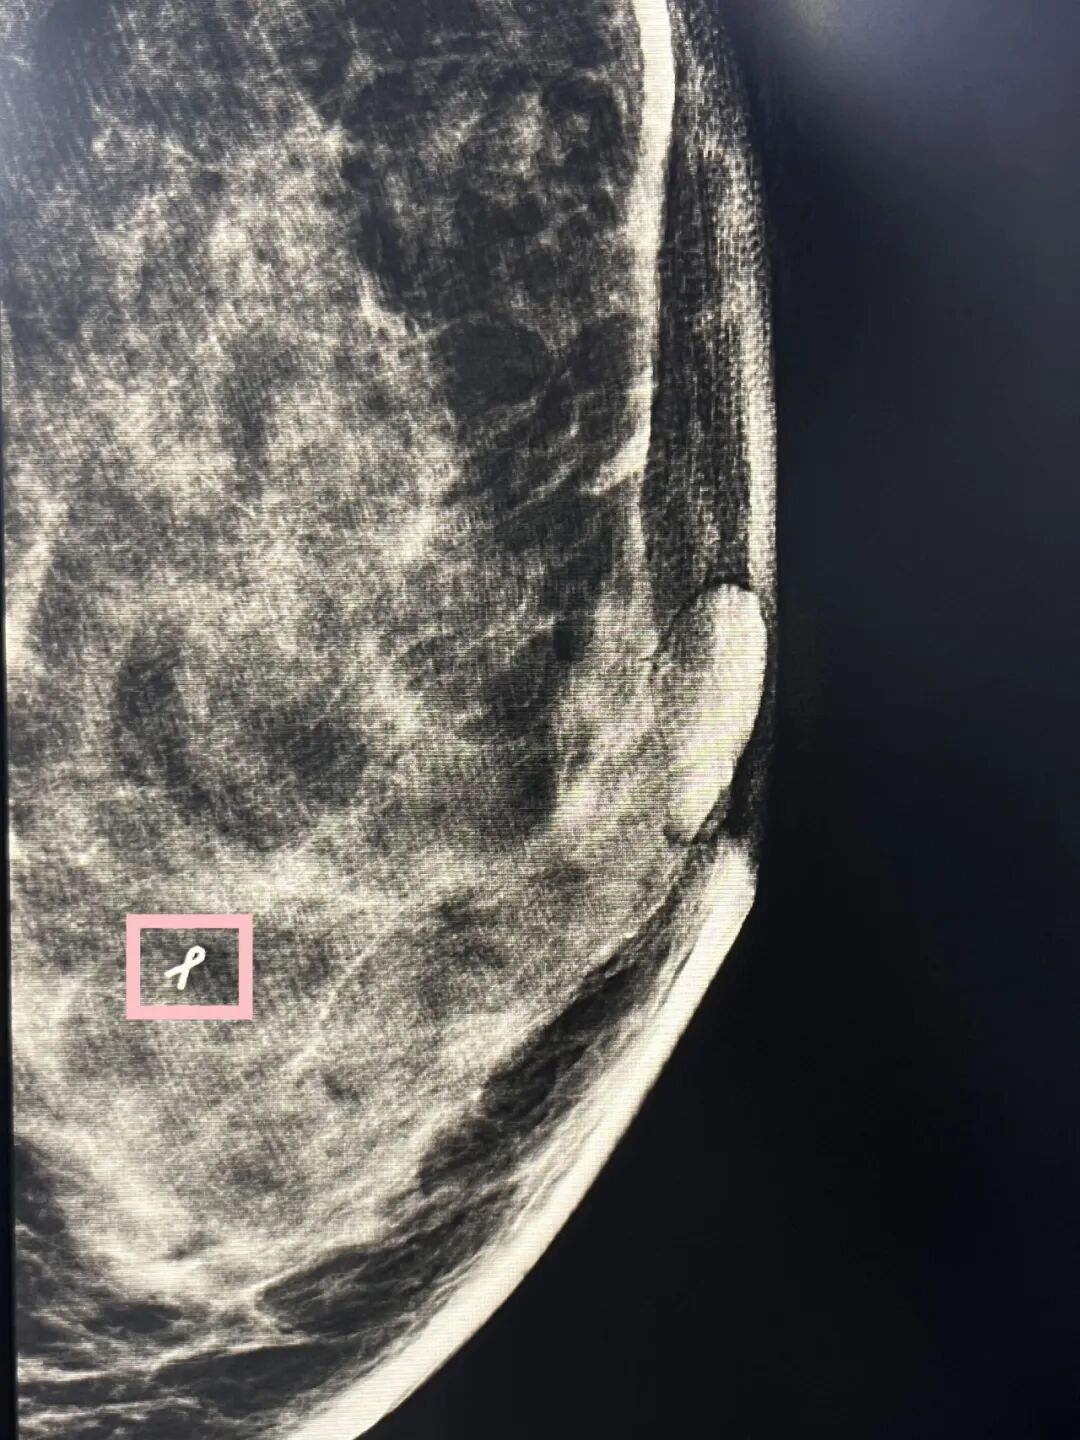

51岁的张女士(化名)在天津市肿瘤医院乳腺影像诊断科乳腺X线查体中发现其左乳内下微钙化(范围6mm),诊断为BI-RADS 4A,触诊阴性。为进一步明确诊断,经乳腺影像诊断科医生检查沟通后,建议行X线引导下真空辅助旋切活检术并放置组织定位标记夹。整个过程仅20分钟左右,张女士配合顺畅,无明显不适。最终活检为良性钙化,排除了恶性,组织定位夹的标记便于后续对术区的随诊观察。

乳腺组织定位标记夹——精准定位随访

该检查与以往不同的是乳腺组织定位标记夹的首次应用

乳腺组织定位标记夹是一种供患者单次使用的组织标志物,并具有在X线、超声及MRI下可视的特点。当病变在影像学上不再可见时,定位标记夹能够指示肿瘤位置,且可以靶向切除肿瘤区域。该技术对于以下三类患者尤为重要:

真空辅助乳腺活检术结束后即刻在活检部位放置乳腺组织定位标记夹,便于后期随时观察病灶有无恶变,避免同一部位重复活检,同时为后续手术及影像学检查提供病灶的精准定位,提高局部控制率